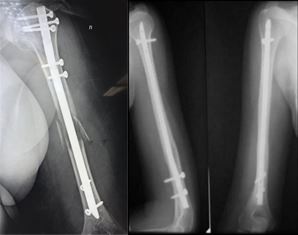

Переломы плечевой кости

Подразделяются на переломы проксимального и дистального эпифизов (концевых участков кости), а также диафиза (центрального отдела плечевой кости, между двумя эпифизами).

Несколько лет назад при переломах проксимального отдела плечевой кости, так называемой хирургической шейки плеча, использовался метод накостного остеосинтеза – пластина с анатомическим дизайном. Данная операция производится из обширного хирургического доступа, что в послеоперационном периоде требует дополнительного внимания и бережного отношения к ранней реабилитации.

В настоящее время специалисты ЦТиО ГВКГ им. Н.Н. Бурденко выполняют остеосинтез подобных переломов по минимально-инвазивной методике через небольшие проколы, без нарушения целостности капсулы сустава и мышц. Это позволяет достичь функционального результата в более сокращенные сроки.

Переломы области диафиза плечевой кости также оперируются по минимально-инвазивной методике с применением интрамедуллярного штифта с блокированием. Различают антеградный (через проксимальный отдел плечевой кости) и ретроградный (через дистальный отдел плечевой кости) остеосинтез. Метод выбора зависит от линии перелома.